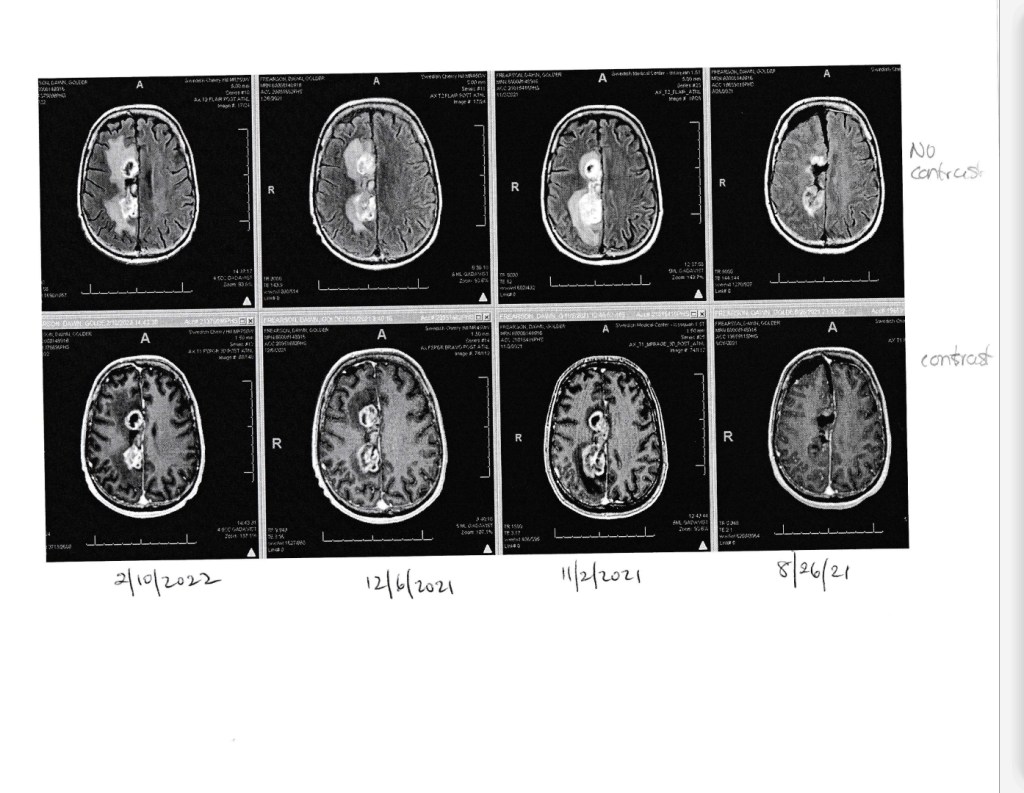

MRI Update

Here are the notes from the MRI. Maybe you can make more sense of them?

FINDINGS:

Prior right parietal vertex craniotomy. Heterogeneous bilobed enhancing mass is redemonstrated medially within portions of the right cingulate gyrus. The more anterior component measures up to 2.4 x 2.0 cm, previously 2.3 x 2.1 cm. The more posterior component measures up to 2.7 x 2.0 cm, previously 3.0 x 2.3 cm. Overall, slightly smaller. Similar enhancement connecting these regions and thinly along a surgical tract extending superlaterally within the right frontal lobe. On perfusion imaging, RCBVs within the more anterior enhancing area is between 2.1 and 3.7 inferiorly. RCBVs within the more posterior area is between 2.2 and 2.5. Similar postsurgical parenchymal loss within the right posterior body of the corpus callosum and some of the overlying right frontal white matter, with associated areas of internal and surrounding hemosiderin deposition.

Non enhancing T2 hyperintensity within portions of the surrounding / overlying right frontal lobe and the right parietal lobe is slightly increased. RCBVs between 1.3 and 1.7. There is similar mild local mass-effect on the superior aspect of the right lateral ventricle. Ventricular caliber otherwise appears on remarkable. No additional, new or worsening enhancement.

Translated this is NO NEW GROWTH and a shrinking of the tumor size.

Bottom Line: The oncologist was very happy with the results. As my sister-in-law Sabine said, Doctor happy, I am happy. We need to keep on doing what we are doing as for now it works!!!!